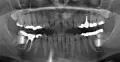

Мне 26 лет, молочные зубы менялись поздно. По личным причинам, когда стал резаться коренной зуб (клык), я не стала вырывать молочный, который был крепким и здоровым. Так на протяжении нескольких лет (очень медленно) прорезался коренной клык и наконец вырос, но на нёбе. Так я ходила с двумя зубками. Никаких неудобств не ощущала. Совсем недавно молочный зуб резко (в течение трёх дней) потемнел.

Помогите, пожалуйста,что нужно делать, удалять оба зуба и ставить мартини? Или после удаления молочного одевать брекеты и ждать пока сдвинется коренной клык?